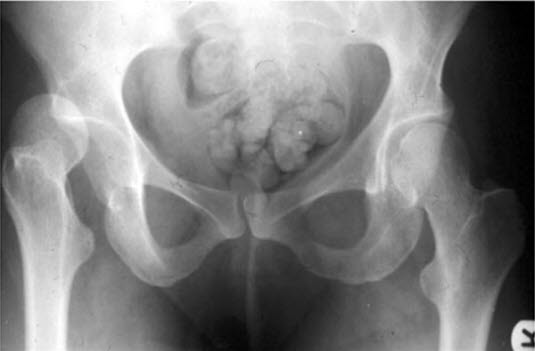

Hofteleddslukasjon, traumatisk

Høyre hofteledd er luksert etter traume.